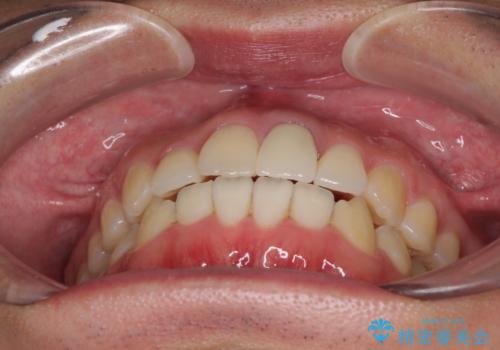

前歯の歯並びとクラウンを改善 インビザラインとオールセラミック

- 前歯の歯並びと不自然な色をした前歯のクラウンを気にして来院された患者様です。

上下前歯の歯列不正はインビザラインにより歯列を整え、その後に、前歯をオーダーメイドタイプのオールセラミッククラウンにて補綴治療することとしました。

初診時には、歯並びを整えることのみを検討されていましたが、歯列が整うにつれて不自然な色合いが気になるようになり、矯正治療を行ってから補綴治療をする計画を受け入れてくださいました。

口元の印象が明るく変わり、患者様には大変満足していただきました。